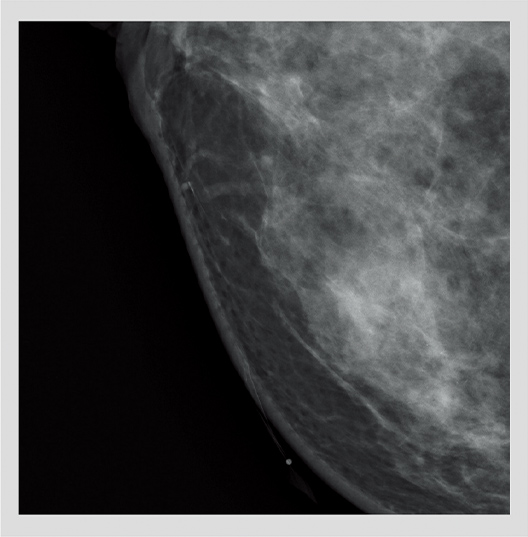

29kV 44mAs 0.83mGy

33mm 102N